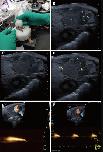

Fig. 3 Echocardiographic imaging can monitor regeneration of X. tropicalis injured hearts in a scar-free manner. A: Representative echocardiography image of the same-age nonapical resection group under B-mode. B: Representative image 5 days after apical resection. The damaged heart with a missing apex (left side of the dashed line) was clearly identified under echocardiography. C: Representative image 10 days after apical resection. D: Representative image 30 days after apical resection. E: Representative image 45 days after apical resection. The regeneration of the injured heart was able to be monitored and justified dynamically by the recovery of morphology and anatomic structure under echocardiographic imaging at 5 days, 10 days, 30 days and 45 days after apical resection. The boundary between the apical region of the regenerated heart and the surrounding tissue was clear, and no adhesion with the surrounding tissue was found at 30 days and 45 days after apical resection. Red arrow: Area of the boundary between the apical region of the regenerated heart and the surrounding tissue. Dashed line: Boundary of the regeneration zone and noninjury zone